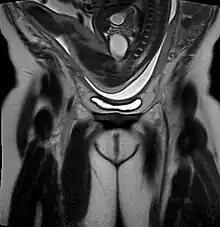

![]() | |

| Drawing of a frank breech from 1754 by William Smellie | |